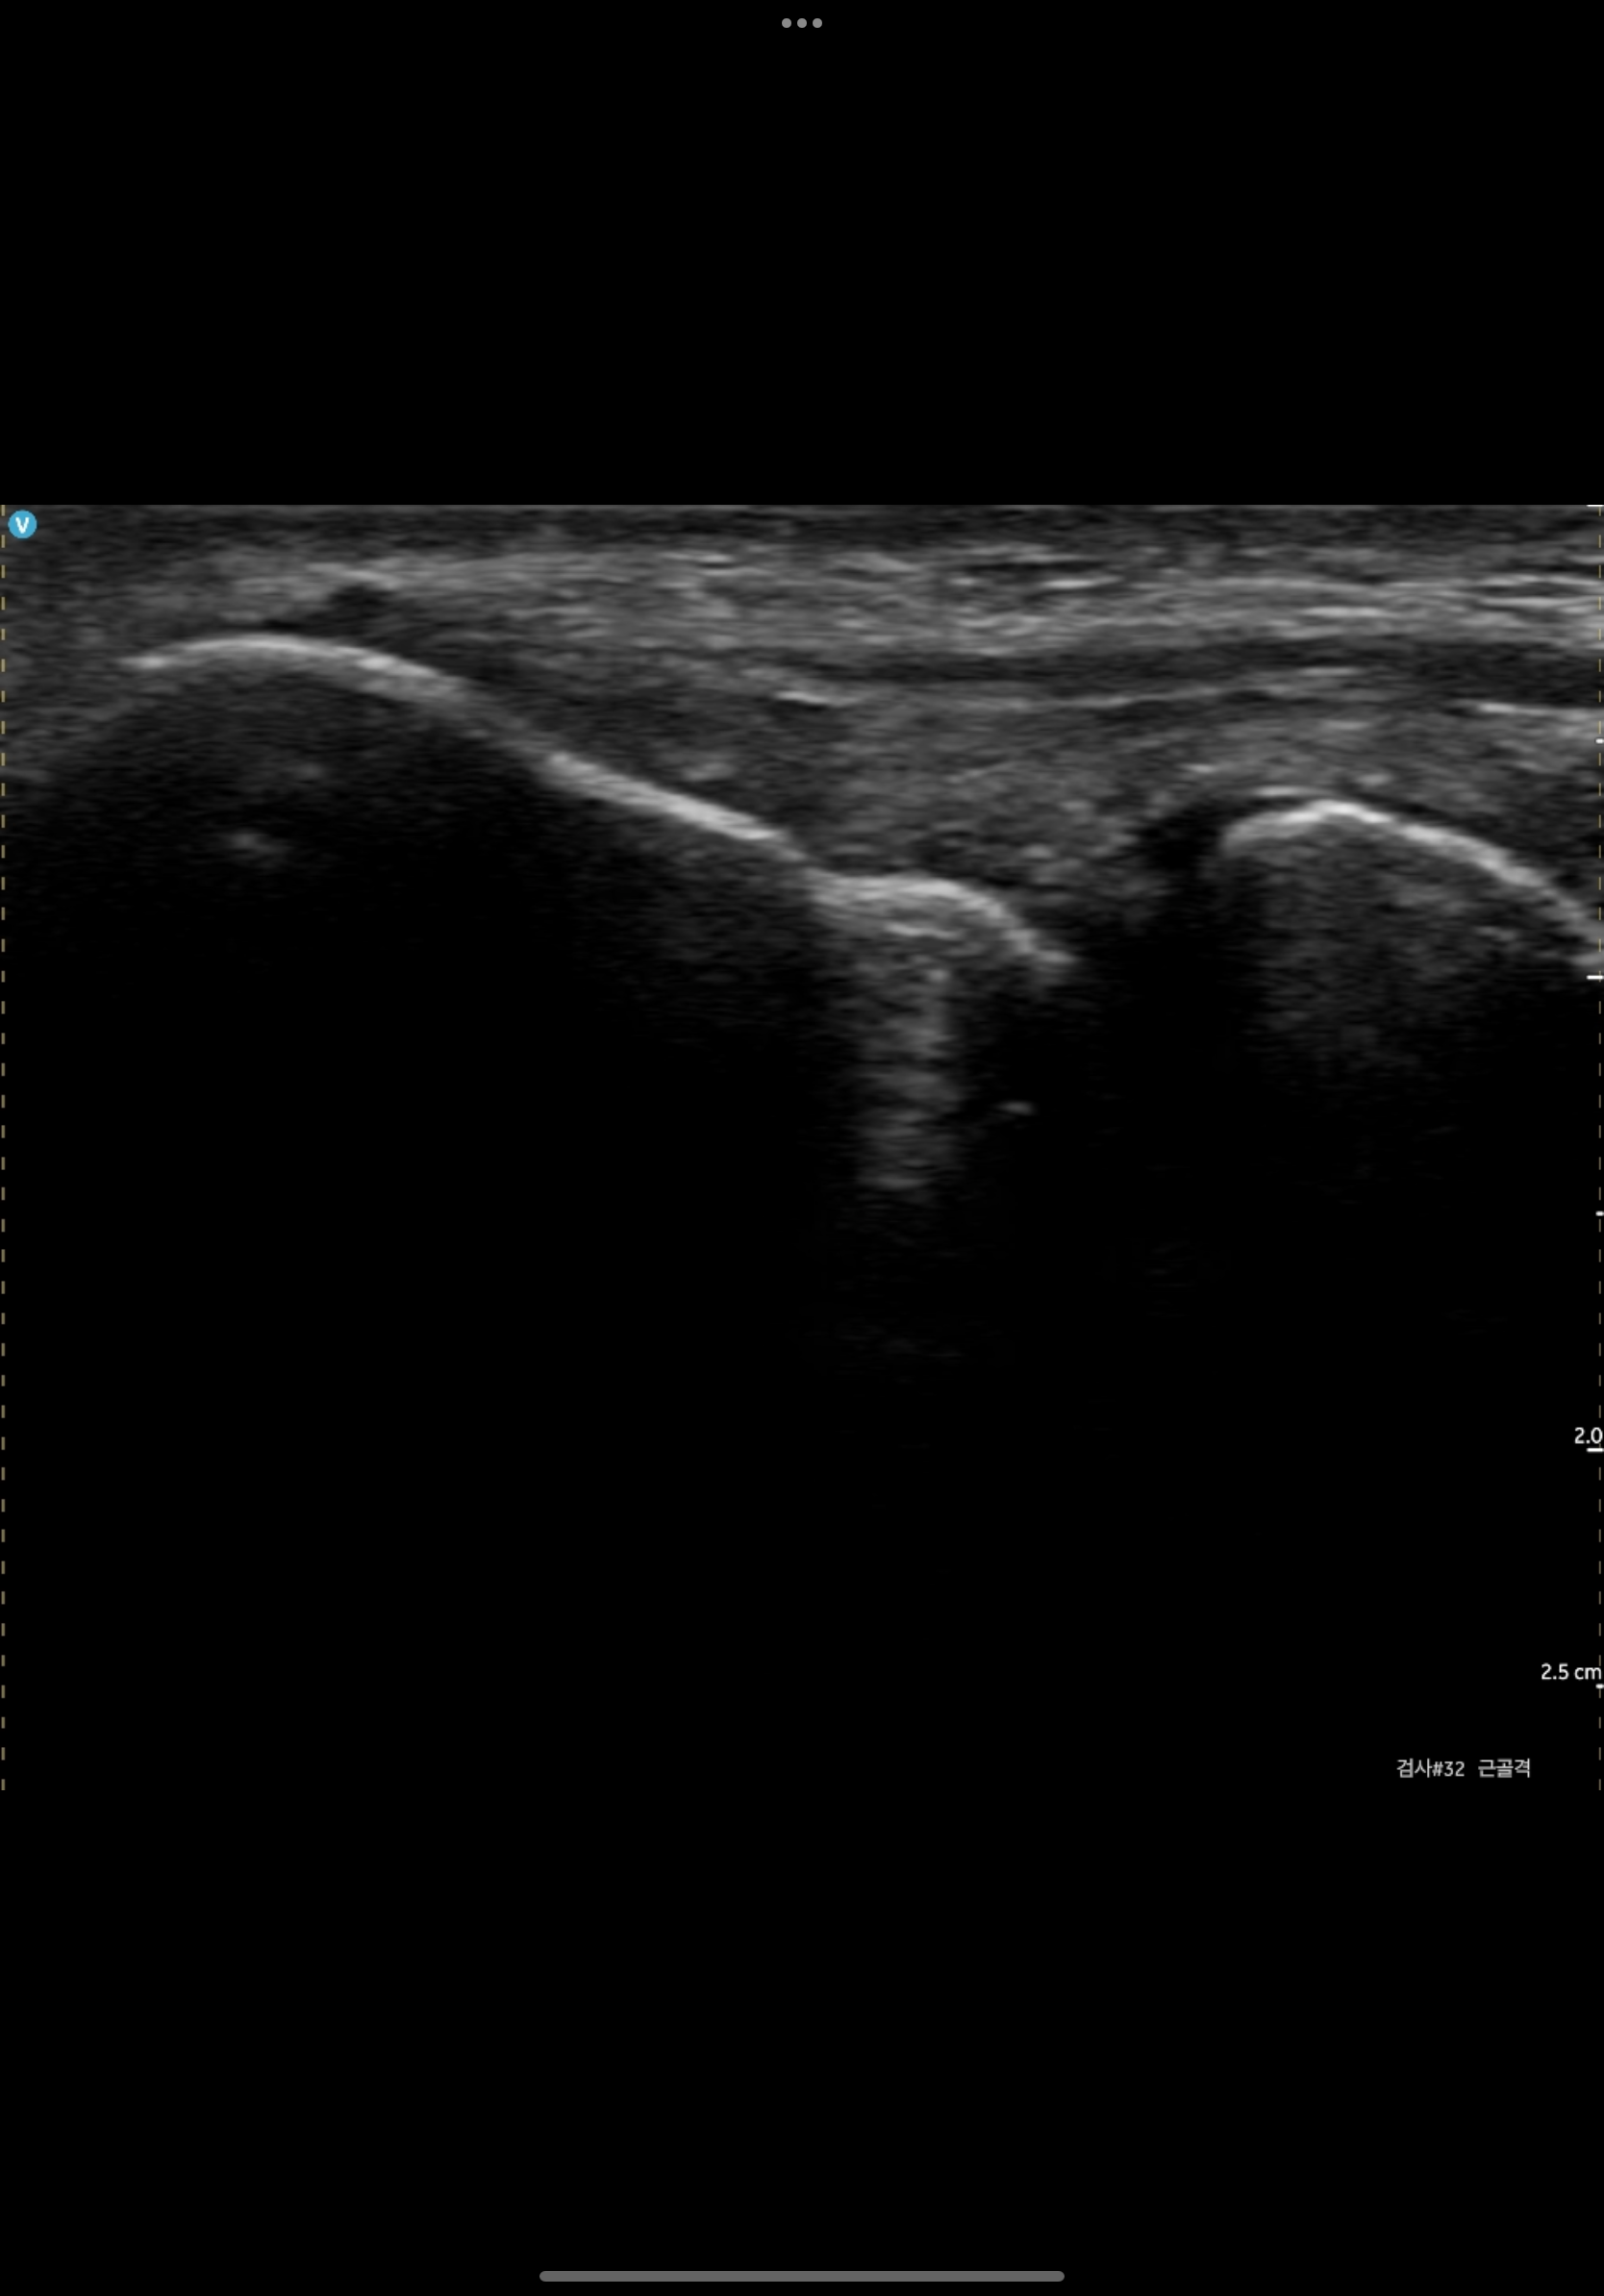

예시 1.Elbow ( 캡쳐 화면 )

예시 2.ANKLE - ATFL ( 캡쳐 화면 )